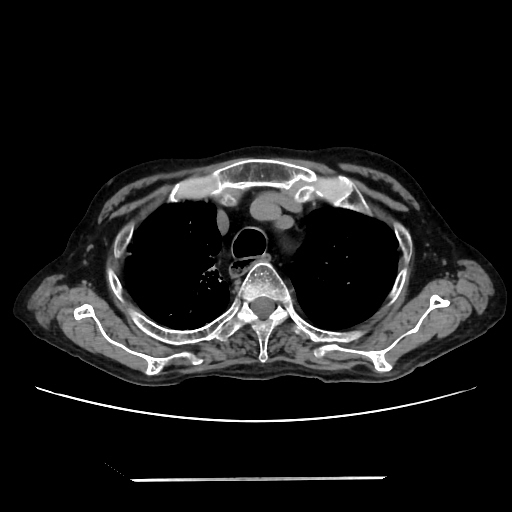

A 58 years old man with....

HRCT done on 17Mar16